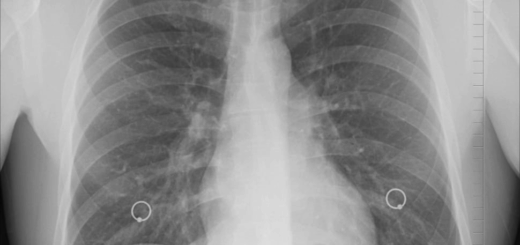

朝から実習 情報・物品管理について注意 10時から放射線科粟田先生来室。画像関係の質疑応答 午後も引き続き実習。空いた時間はCT課題に活用された...